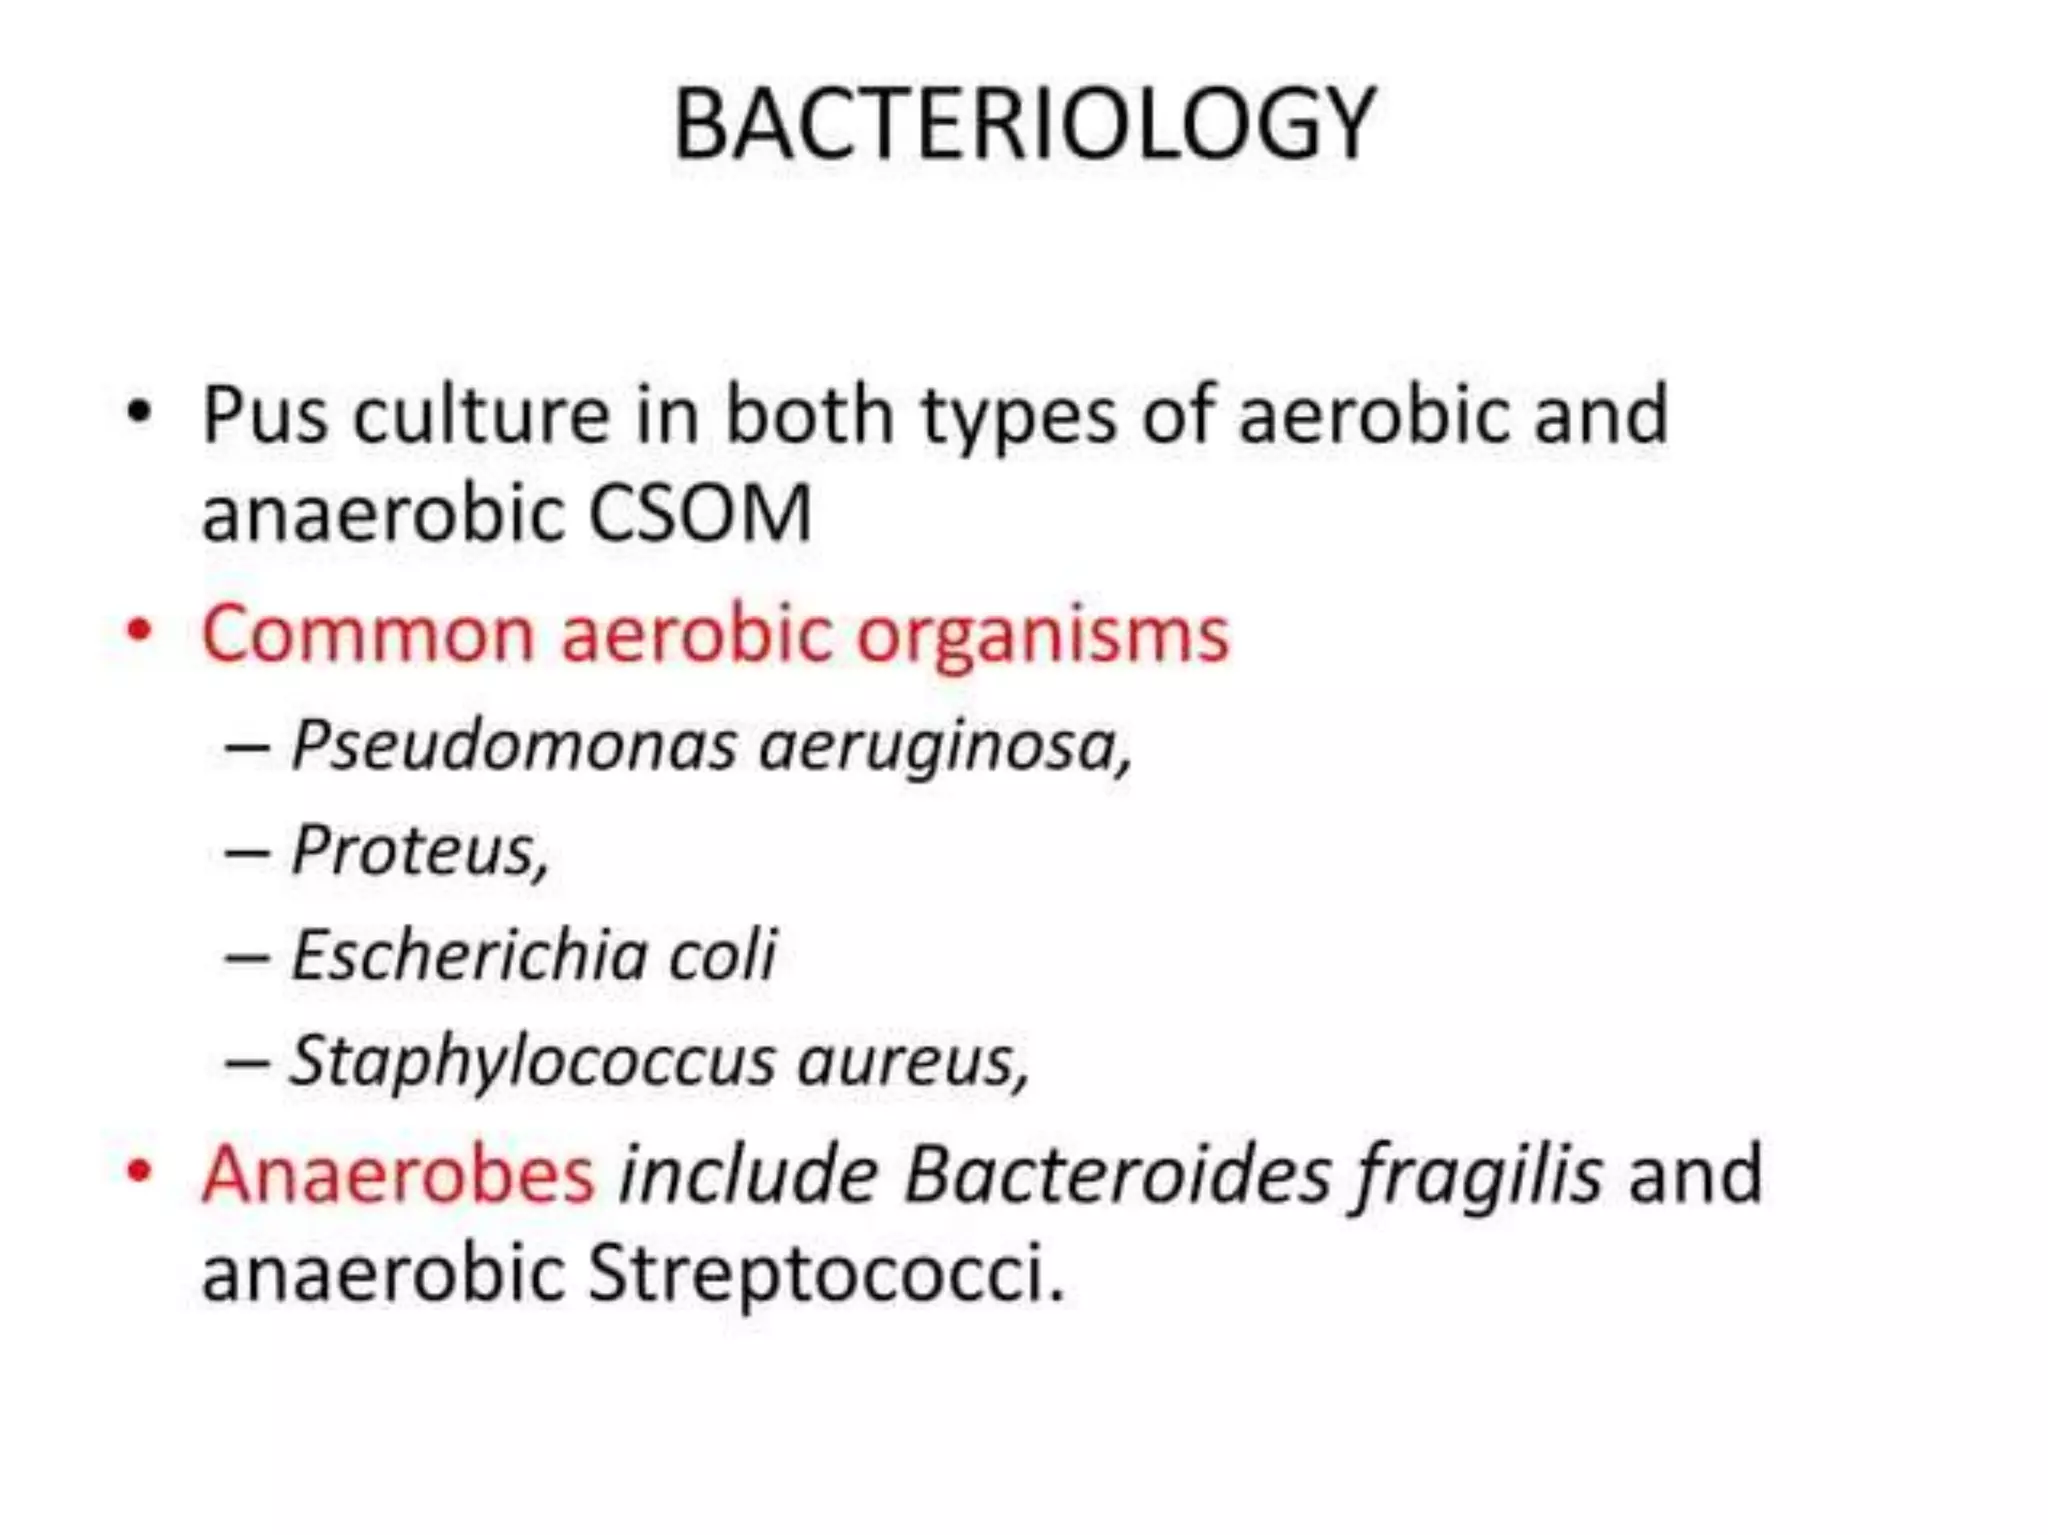

Chronic otitis media is a chronic inflammation of the middle ear and mastoid cavity that presents with recurrent ear discharge through a perforated eardrum. It has several subtypes depending on the state of the eardrum perforation and epithelium. It can be caused by prior acute otitis media, genetics, environment, eustachian tube issues, gastroesophageal reflux disease, craniofacial abnormalities, or immune deficiency.